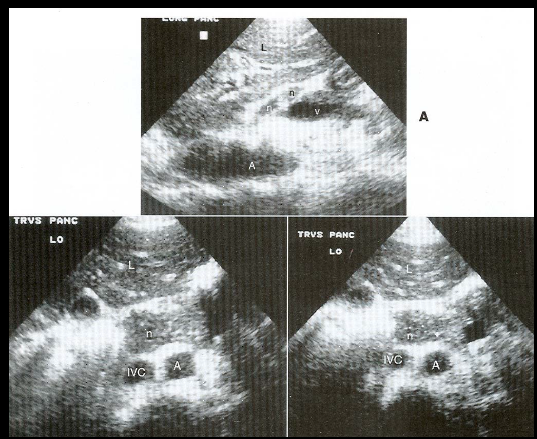

what are these examples of?

peripancreatic lymph nodes (pt has history of lymphoma)

same below